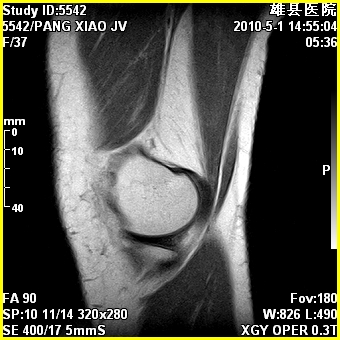

标题: MRI2894:患者右膝关节疼痛两月余,无明显外伤史 [打印本页]

标题: MRI2894:患者右膝关节疼痛两月余,无明显外伤史

右股骨下端前内侧类圆形异常信号,位于干骺端,呈长t1长t2改变,但信号不均,t1图上病灶中心见小片状稍高信号影,t2图上见散在稍低信号影,stir像呈高信号,因病灶较小,缺乏特征性改变,结合患者年龄及部位,考虑嗜酸性肉芽肿可能性大。胫骨关节面下的小囊状异常信号,如果一元论考虑则为嗜酸性肉芽肿,不过发生在这个部位的少见,二元论考虑为邻关节骨囊肿。半月板与前后交叉韧带均未见异常。

右股骨下端前内侧干骺端囊性良性病变,考虑 1内生软骨瘤 2骨囊肿 3肉芽肿。